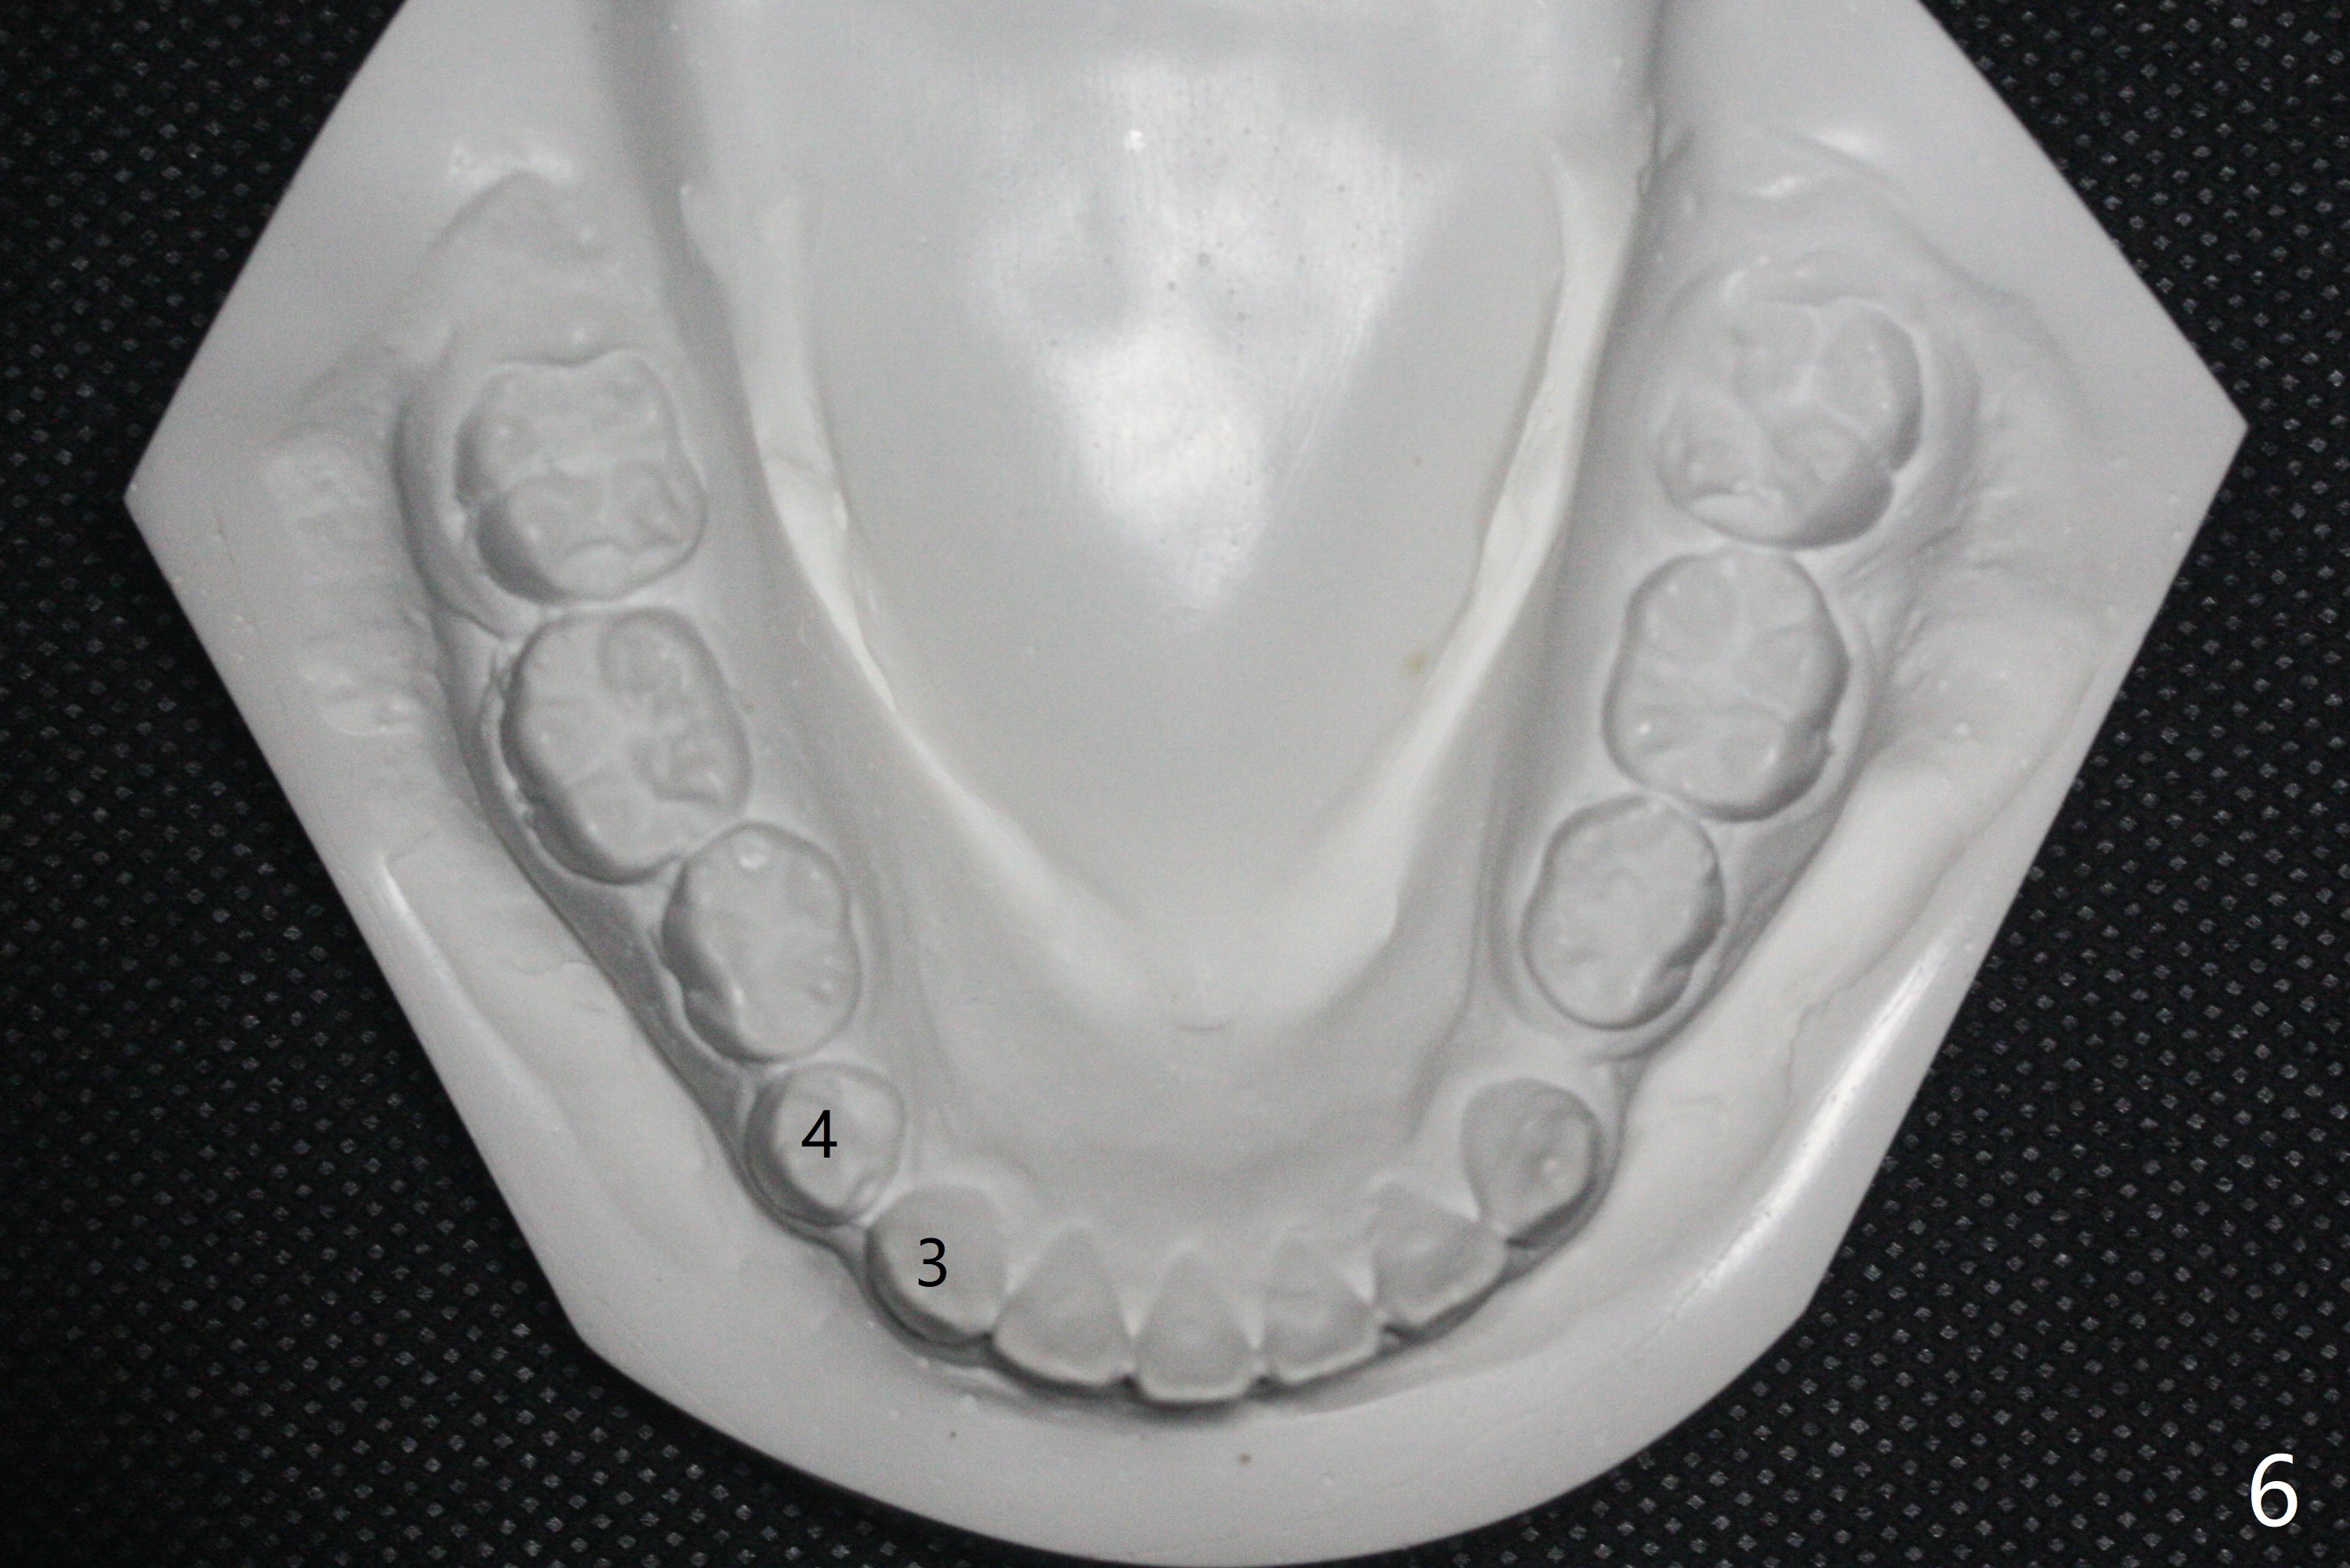

One-year-8-month orthodontic treatment reduces anterior overjet (Fig.1 (double arrows),1', with facial profile improvement), corrects right 1st molar cross bite (Fig.2,2') and dental midlines (Fig.3,3'), closes the diastema between UL3 and 4, extrudes UL5 (Fig.4,5,4',5'), and increases space for future implant at LL4 (Fig.6,6'). In fact large arches with distemata make the treatment possible! Extrusion of UL5 leads to root development (Fig.7, 7' (R)). The increased space at LL4 (Fig.7' *) appears insufficient for an implant.